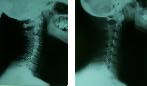

横から見た場合: